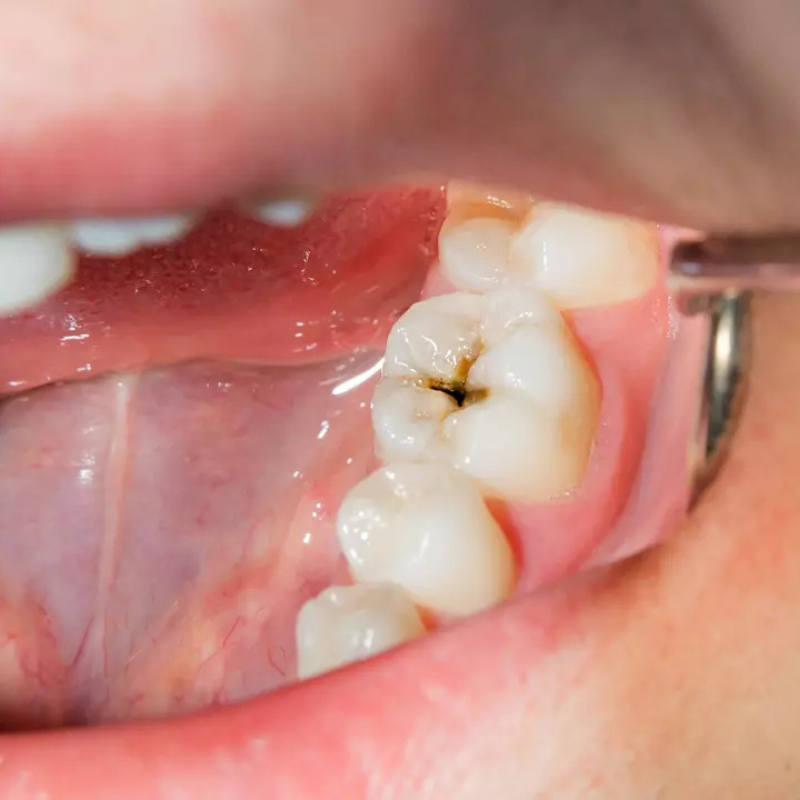

Gros plan sur une dent cariée illustrant les effets de la plaque bactérienne et l’importance d’une bonne hygiène bucco-dentaire avec DentalPro Smile™.

A cavity is a progressive lesion caused by the acid attack from bacteria present in dental plaque. Without treatment, it gradually destroys the enamel, dentin, and can reach the pulp, causing pain and infections.

1. White stain on the enamel (beginning invisible to the naked eye).

2. Superficial cavity : small cavity.

3. Deep cavity : pain when chewing.

4. Pulp involvement : infection, abscess, sometimes tooth loss.